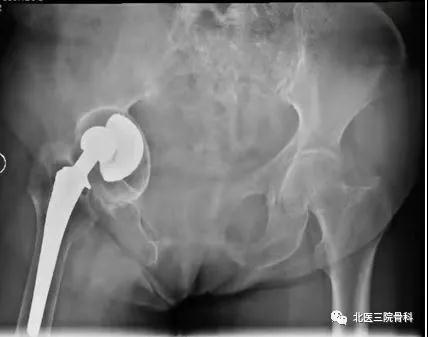

翻修患者为70岁的老年女性,该患者右侧全髋关节置换术后16年,髋臼侧假体松动移位,合并严重的骨缺损和右下肢短缩(图5),诊断“右髋关节置换术后假体无菌性松动”。手术前通过对CT影像进行降噪、分割、骨缺损范围识别后,对骨缺损修复和髋臼假体位置进行3D规划,手术是由田华主任和李锋教授共同完成(图6)。

术中,导航系统不仅可以追踪髋臼磨锉、假体位置和前倾角/外展角等关键角度信息,还可以对补块位置进行示踪(图7),将补块和假体安放的位置和角度精确到1mm和1°,从而最大程度地避免了人工操作的误差和对重要生理结构的副损伤,大大提高了骨缺损修复的精准性和手术操作的安全性。术后患者恢复良好,影像学显示补块及假体位置满意(图8)。第二天开始下地活动。

图8 患者术后X光片,补块和假体位置满意,精准实现了术前规划